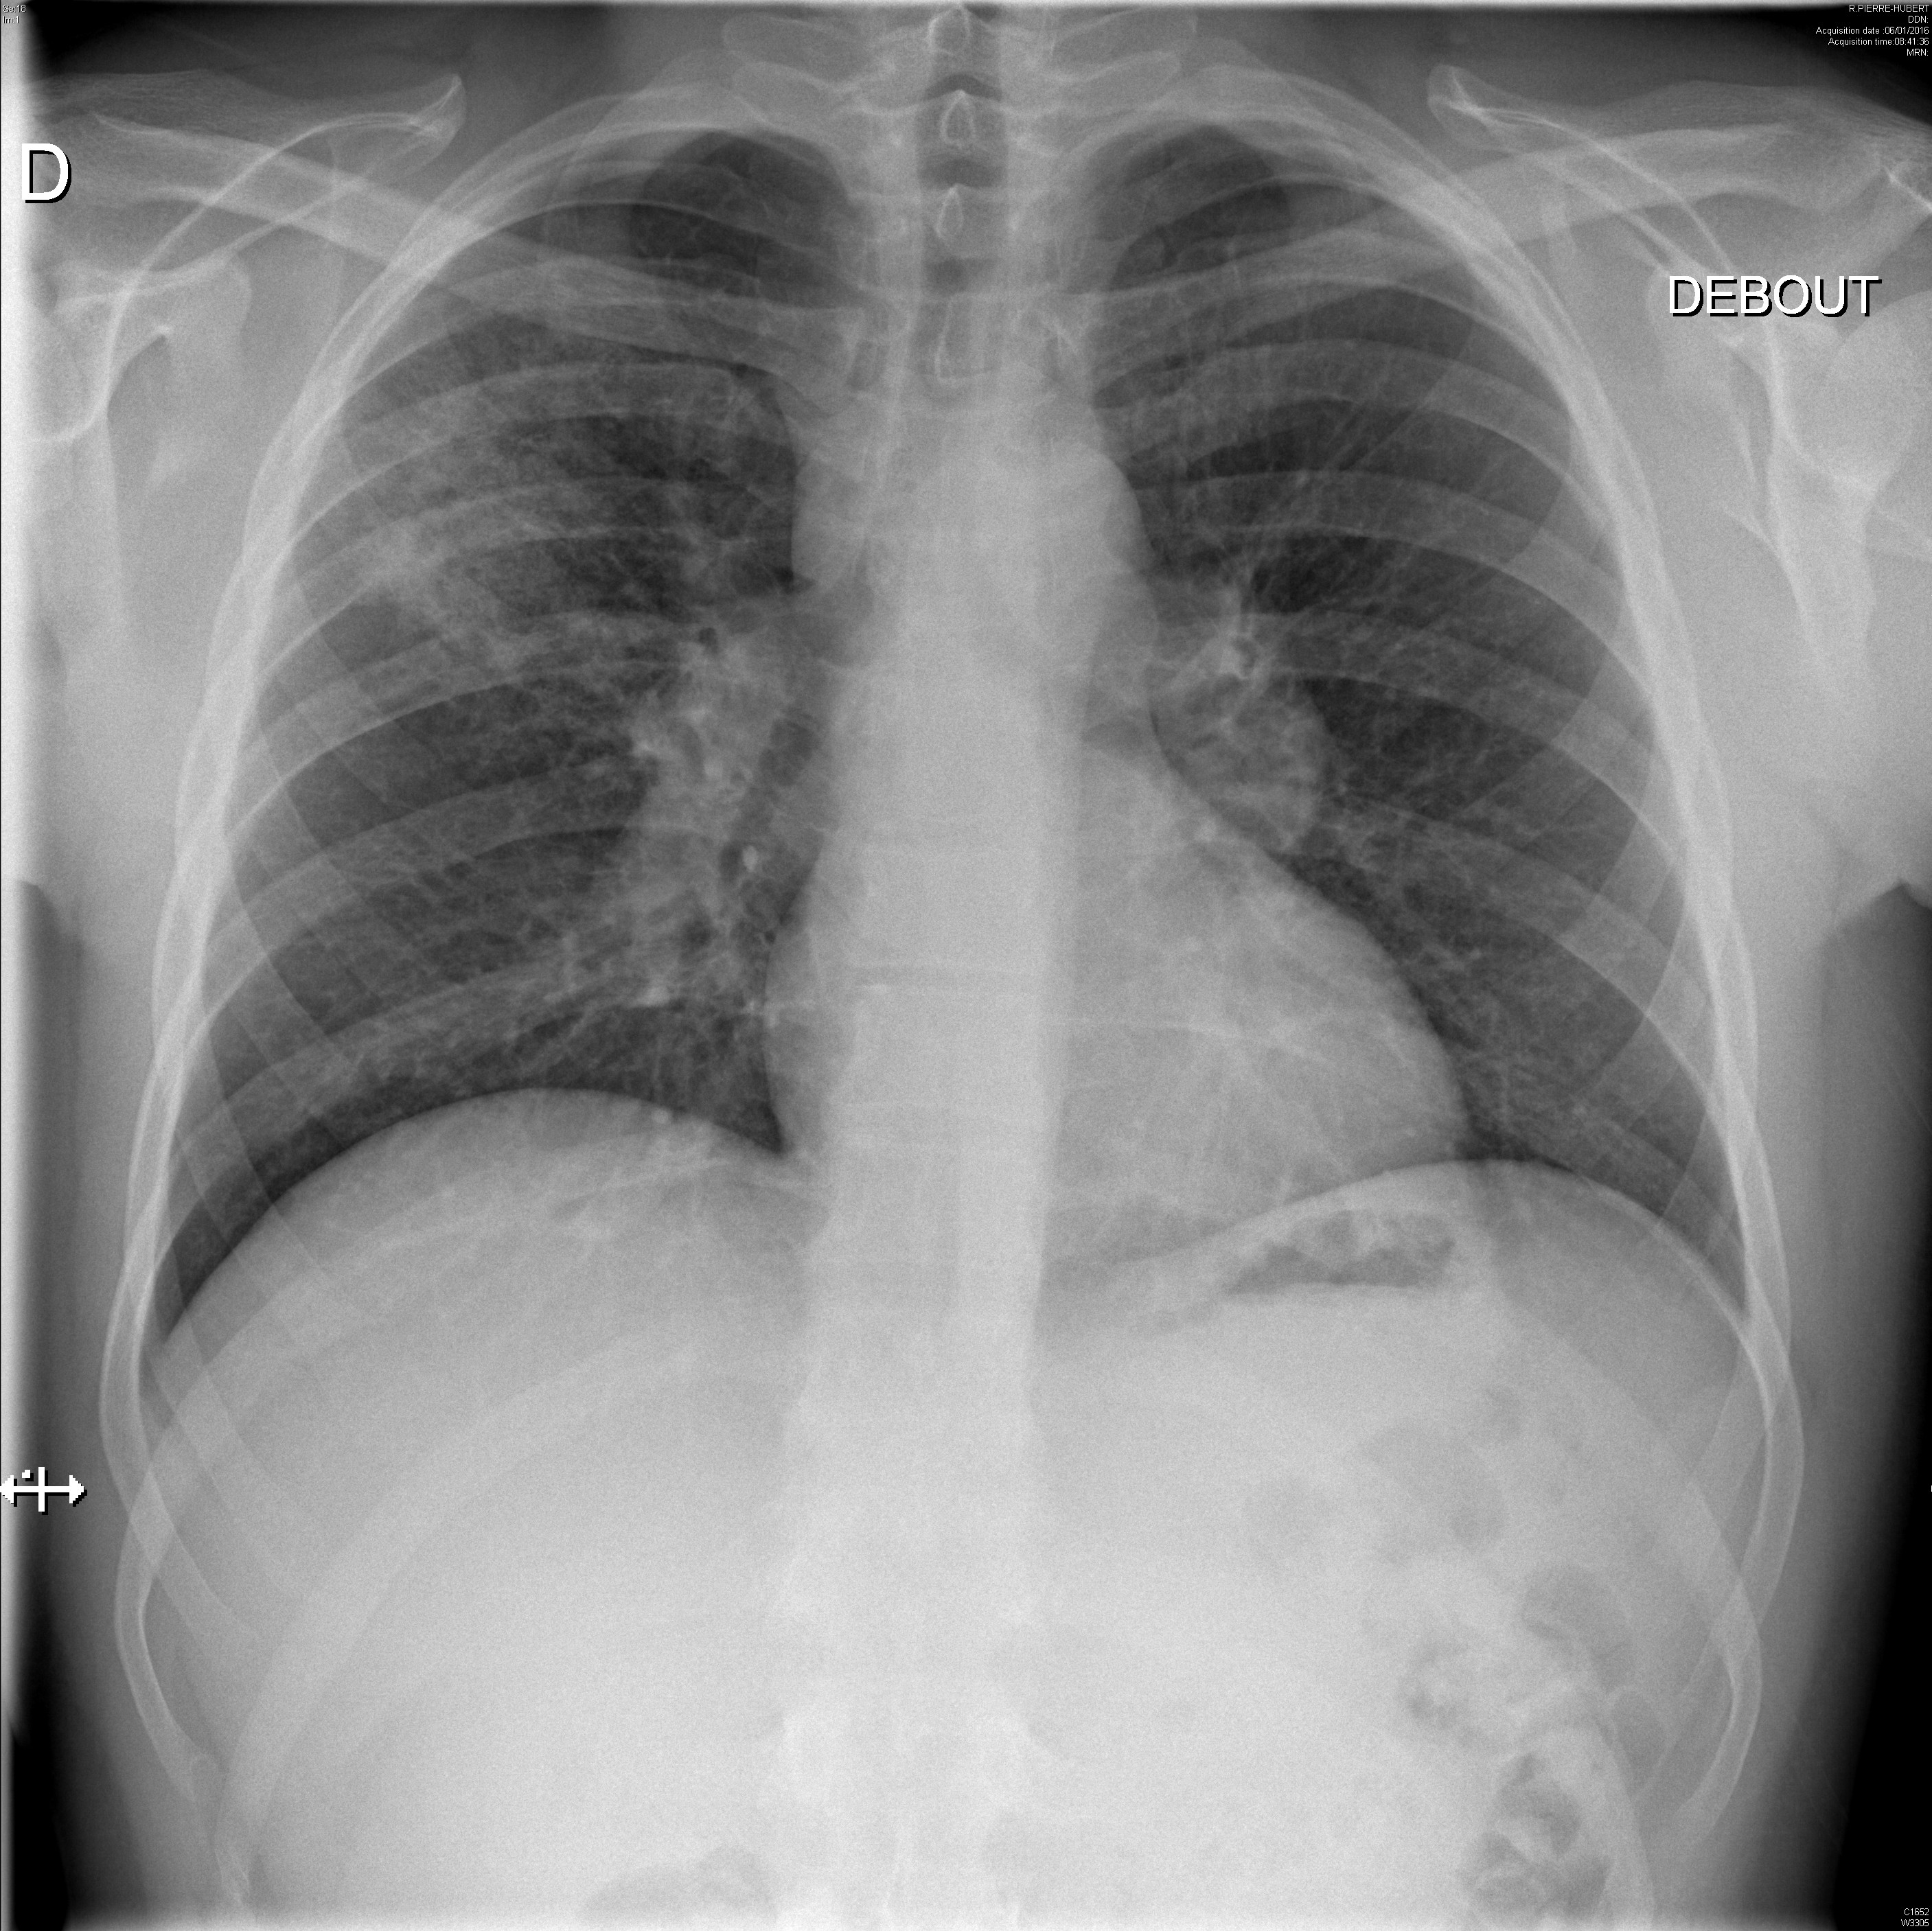

Syndrome interstitiel et adénopathies médiastinales dans le cadre d'une sarcoïdose systémique